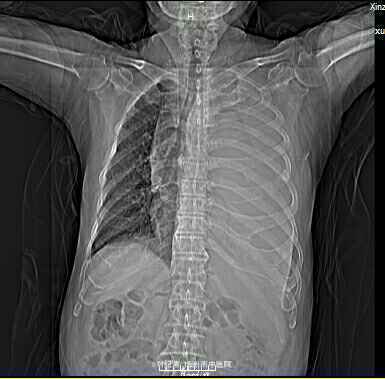

查体:ECOG评分:3分,生命指征平稳,浅表淋巴结未触及明显肿大,双眼睑无水肿,唇无发绀,颈软,双侧胸廓对称,左肺语颤增强,左肺呼吸音消失,右肺呼吸音粗,可闻及哮鸣音,心律齐,腹平软,肝脾肋下未触及,移动性浊音阴性,肠鸣音3次/分,双下肢无水肿。 辅助检查:血常规(2016.1.1):WBC:10.6*109/L,RBC:4.69*1012/L, PLT:165*109/L ,HGB:167g/L.生化(2016.1.1):谷丙转氨酶11U/L,谷草转氨酶11U/L,总蛋白60g/L,白蛋白33g/L,尿素:9.8mmol/L,肌酐:123umol/L,尿酸:251 umol/L,血糖:7.37 mmol/L;电解质:钾:4.79mmol/L,钠:123.5 mmol/L,氯:85.7 mmol/L,钙:2.03 mmol/L。肺部CT(2016.1.1):左肺完全萎缩,左侧胸腔大量积液,右肺未见异常,纵膈轻度右移,未见明显肿大淋巴结。

诊断: 1.左肺癌 左侧胸腔积液 左肺不张;2.2型糖尿病;3.低钠、低氯血症;4.低蛋白血症 治疗 完善检查,予以胸腔穿刺置管引流胸水以减轻心肺负荷,静脉给予抗感染、祛痰、止咳、平喘、提高免疫、扶正抑瘤、营养支持、调节电解质平衡及对症治疗。